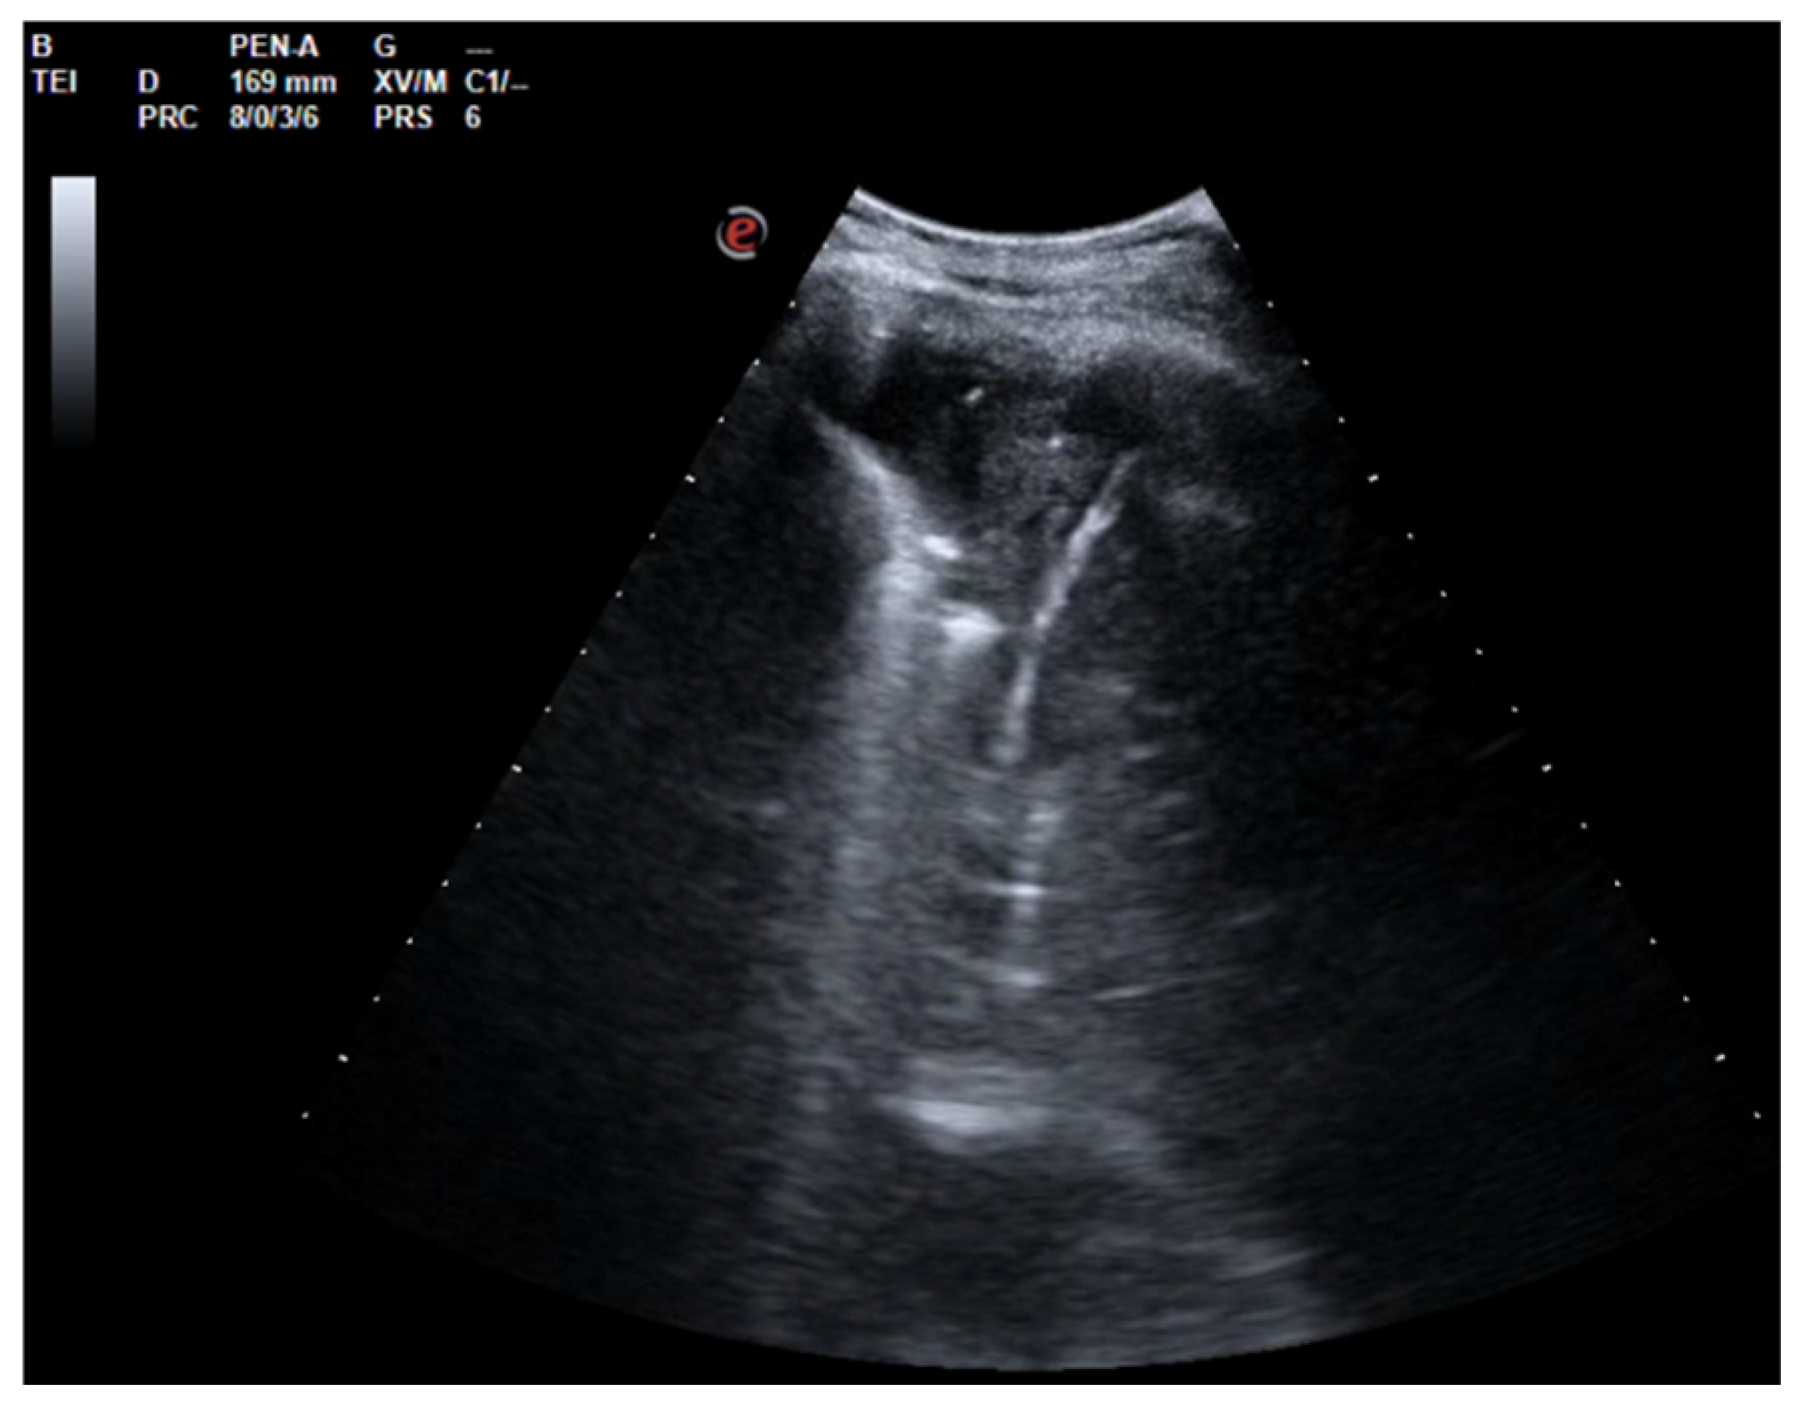

A 26-year-old man was admitted to our hospital for worsening dyspnea at rest and pain in the right hemithorax. The patient complained of a fever (39.5 °C) and productive cough for about 1 week, with mild hemoptysis in the days prior. His medical history included bilateral bronchiectasis and bronchial asthma, for which he received inhalation therapy with a long-acting antimuscarinic agent, long-acting bronchodilator, and inhaled corticosteroid. He had no family history of respiratory disease and had been tested for cystic fibrosis transmembrane regulator (CFTR) gene mutations, with negative results. The patient did not smoke cigarettes, drink alcohol, or use recreational drugs. An arterial blood gas (ABG) analysis showed acute hypoxemic normocapnic respiratory failure; therefore, oxygen therapy with a 28% FiO2 via a Venturi mask was administered. Chest radiography showed an area of opacification at the right base. Empiric antibiotic therapy with 12 mg/kg teicoplanine (Q8H) and 4.5 g piperacillin/tazobactam (Q6H) was then started on suspicion of community-acquired pneumonia. Blood tests upon his admission showed leukocytosis (WBC 18.84 × 109 cells/L) with predominant neutrophils (14.5 × 109 cells/L). Legionella and pneumococcal antigens in his urine were negative. Blood cultures after 72 h were negative. Chest ultrasonography revealed a multiloculated effusion (Figure 1).

Figure 1. Chest US at admission. Multiloculated pleural effusion.